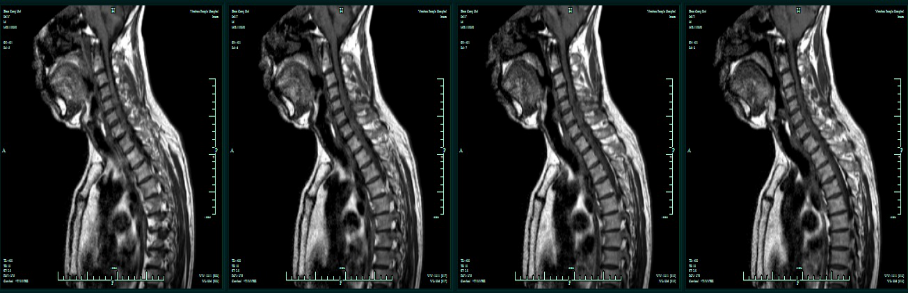

MRI增强:C4-T1椎管内髓外占位,淋巴瘤可能性大。

术前T1平扫

术前T2平扫